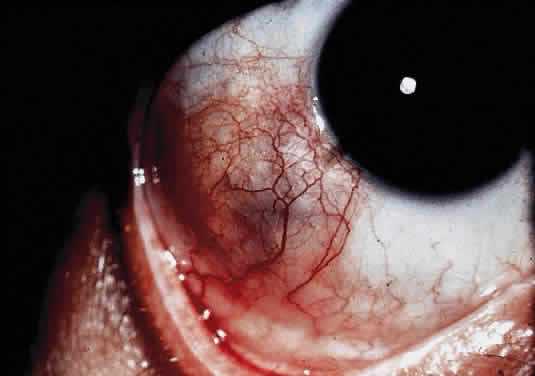

OCULAR FINDINGS. The outstanding clinical feature common to all three phenotypes is the corneal and conjunctival cystine crystal deposition (Figs. 3 and 4). Photophobia is often the only presenting visual symptom; this may be incapacitating and associated with blepharospasm.

Corneal deposits appear as a layer of homogeneously distributed, fusiform or needle-shaped, iridescent crystals situated in the stroma beneath the epithelium. In the infantile form, anterior crystal deposition begins early in life (between 6 and 15 months of age) and proceeds posteriorly as the patient ages; deposition advances more rapidly in the periphery. The anterior location of the crystals may be associated with recurrent erosions.33 The depth of the stromal deposition and the density of crystals is always greater peripherally than centrally. More and larger crystals occur in the superficial stroma. No visual impairment occurs at this early stage. By the age of 7 years, most patients have crystals, either within or on the endothelial surface34,35; markedly decreased corneal sensitivity is also present.36 The spherical contrast sensitivity function is significantly lower in infantile cystinosis than in age-matched controls.37

The conjunctiva has a ground-glass appearance. Polychromatic, polymorphic, rectangular, or rhomboidal crystals can be seen with the biomicroscope.